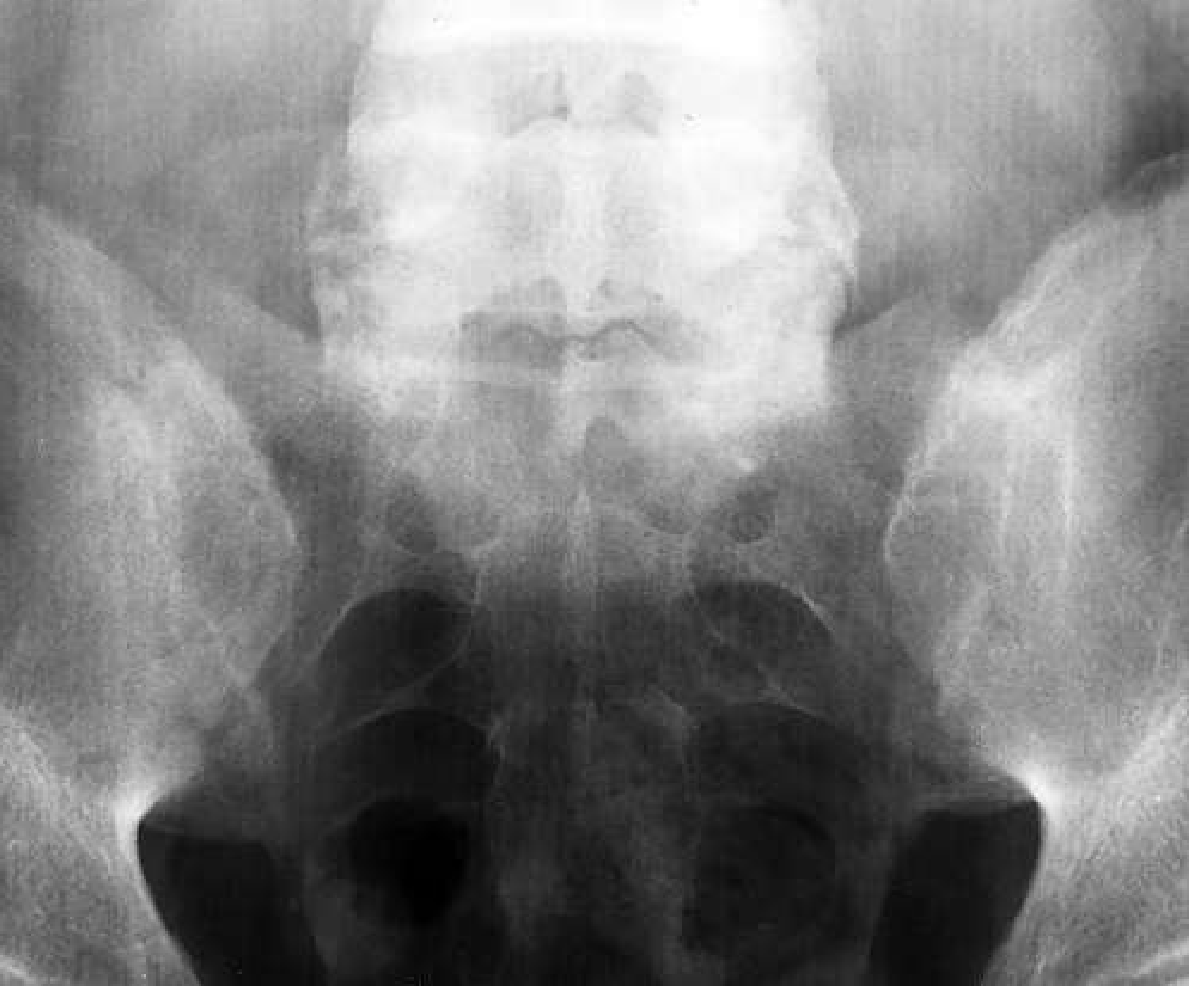

Bilateral symmetrical sacroiliitis on plain X-ray

Plain film pelvis: bilateral symmetrical sacroiliitis in AS. — Goldman-Cecil Medicine

Key radiologic distinction from other SpA:

FeatureASReactive/Psoriatic Arthritis

SacroiliitisBilateral, symmetricalUnilateral/asymmetrical

SyndesmophytesSmooth, marginal, verticalCoarse, non-marginal, bulky